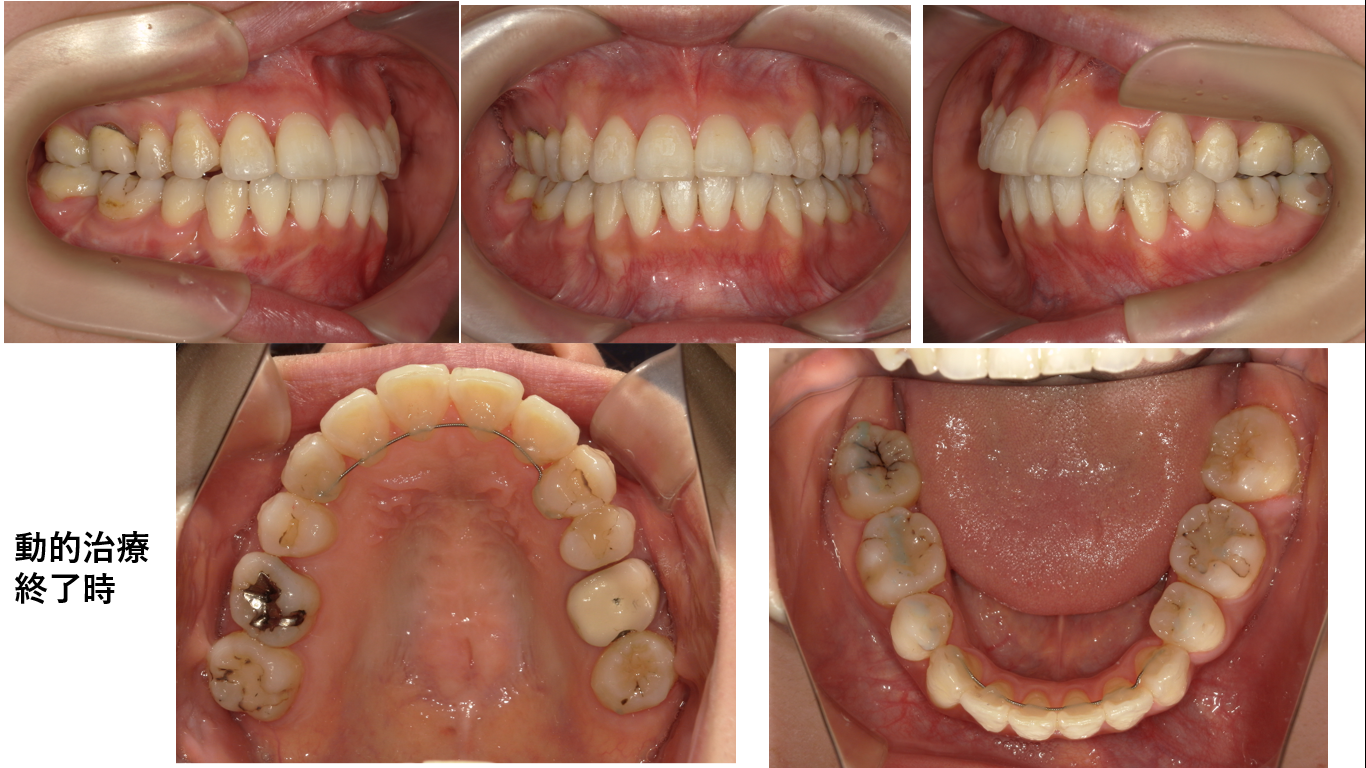

上顎右側犬歯は抜歯されていました。初診の下顎右側7番が銀歯ですが、動的治療終了時の下顎右側7番は白い歯です。これは銀歯を白いに歯に替えたのではありません。根管処置された下顎右側7番のメタルコアが極めて大きく予後不良と判断され抜歯されたからです。抜歯の後、埋伏歯である右側8番は牽引されて7番の位置へ排列されました。

下顎右側8番埋伏歯を牽引するのに2年6か月かかりました。

何はともあれこの症例の場合、時間こそかかりましたが、歯根の長さも十分あり歯根吸収が無く歯冠の形態も良好です。インプラント1本の値段からすれば格安で自分の歯で咬めるのですから患者さんからすれば良い買い物でした。